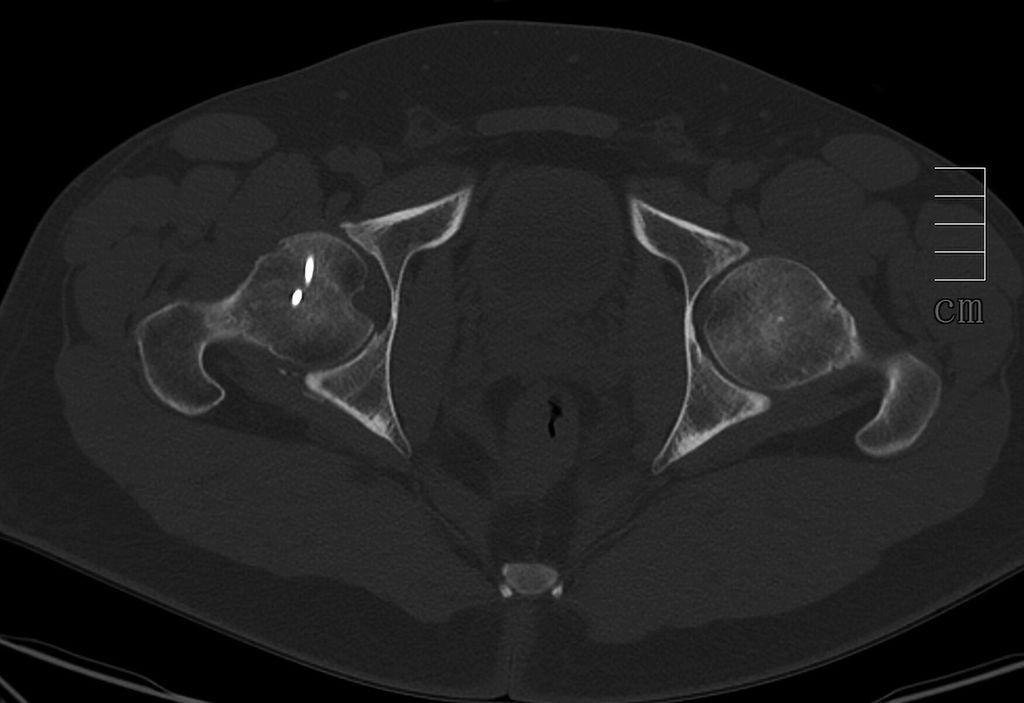

Abb. 3: Zur präoperativen Planung und zur Beurteilung des geschlossenen Repositionsergebnisses ist der Goldstandard die Computertomografie

Neben der klinischen Erstuntersuchung und Anamnese umfasst die Diagnostik die konventionelle native Röntgendiagnostik des verletzten Hüftgelenkes mit Standardaufnahmen im a.-p. und axialen Strahlengang (Abb. 1, 2) sowie gegebenenfalls die Anfertigung von Ala- und Obturatoraufnahmen. Obligatorisch empfehlen wir die Anfertigung eines Hüftübersichtsröntgens und gegebenenfalls, sofern möglich, auch eine Faux-Profil-Aufnahme. Zur präoperativen Planung und zur Beurteilung des Repositionsergebnisses ist der Goldstandard die Computertomografie (Abb. 3) mit Anfertigung einer 3D-Rekonstruktion. Im Rahmen der Notfalldiagnostik spielt die Magnetresonanz keine wesentliche Rolle. Im Hinblick auf die Diagnostik sekundär auftretender Komplikationen ist jedoch die Bedeutung des MRT unumstritten.

Die Therapie der Pipkin-Fraktur sollte notfallmäßig die Reposition der Hüftluxation, sofern eine solche vorliegt, innerhalb von 6 Stunden nach dem Unfallereignis beinhalten. Die anatomische Wiederherstellung der Belastungszone (Abb. 5, 6) sowie die osteosynthetische Refixation können als verzögerter Primäreingriff in Abhängigkeit vom Gesamtzustand des Patienten innerhalb der ersten 14 Tage erfolgen. Entscheidende Faktoren in der Therapiefindung sind das Patientenalter, der Aktivitätsgrad, die Begleitverletzung sowie bereits vorbestehende degenerative Veränderungen des Hüftgelenks. Der minimalinvasive anteriore Zugang eignet sich aufgrund des Überblicks über das vordere Acetabulum sowie den ventralen Hüftkopf hervorragend zur Osteosynthese von Pipkin-I- und -II-Frakturen. Anders als bei der primären Endoprothetik achten wir auf den Erhalt großer Anteile der ventralen Hüftgelenkskapsel sowie der begleitenden Äste der Arteria circumflexa femoris, um eine operationsbedingte zusätzliche Durchblutungsstörung des Hüftkopfes zu vermeiden. Nachteilig wirken sich Frakturausläufer im Acetabulum aus, die über den anterioren Zugang nur durch Erweiterung zugänglich sind. Daher ist es obligat, immer eine präoperative Computertomografie zur Operationsplanung durchzuführen, da letztendlich der Frakturtyp den Zugang vorgibt. Nach Swiontkowski et al. kommt der Zugangswahl nur eine sekundäre Bedeutung für das Endergebnis zu. Allerdings ist bei Verwendung des anterioren Zuganges die Operationszeit kürzer, der Blutverlust geringer sowie die technische Durchführung der Refixierung erheblich einfacher. Gemäß der aktuellen Literatur werden nach minimalinvasiver direkt anteriorer operativ versorgter Pipkin-II-Fraktur etwa 80% zufriedenstellende Langzeitergebnisse berichtet.